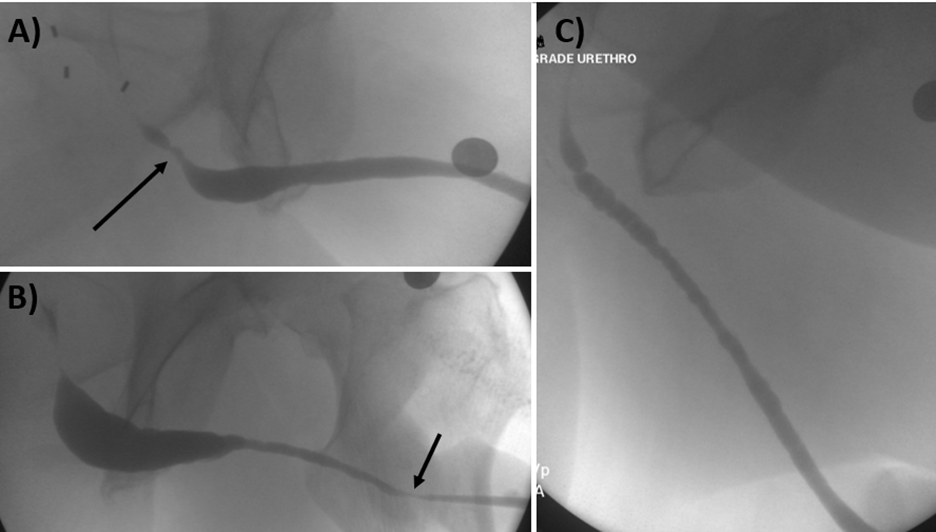

If obstructive voiding symptoms are present, along with a reduced flow rate on uroflowmetry +/- an elevated post-void residual volume on bladder ultrasound, further evaluation of the urethra using imaging modalities is indicated.3 Imaging studies are essential not only to diagnose the stricture, but also to assess the length of the stricture, which can inform operative planning.3,6 A retrograde urethrogram (RUG) and voiding cystourethrogram (VCUG) can be used to view the full length of the urethra.2,6 While VCUG alone is not sufficient to delineate the full male urethra, it can effectively visualize the entire female urethra.3 If VCUG and RUG cannot provide a definitive diagnosis of urethral stricture disease, cystoscopy, also known as urethroscopy, can elucidate the characteristics of a stricture.13 Urethral ultrasound is also an acceptable, though less common, method of evaluating stricture disease. These studies can help identify the stricture and determine its location, length, and severity; with visible narrowing present in the urethral lumen at the site of the stricture (Figure 4 and Figure 5).6

Figure 4: Identification of a urethral stricture using cystoscopy (A), retrograde urethrogram (B), and voiding cystourethrogram (C). Gray-scale ultrasound (D) and contrast-enhanced ultrasound (E) of the urethra can also evaluate stricture disease.

Figures were provided as a courtesy by Dr. Paul H. Chung, Thomas Jefferson University, Philadelphia, PA.

Figure 5: Localization of urethral strictures using retrograde urethrogram. A) Urethrogram from a patient with a bulbar urethral stricture, with the arrowhead indicating the region of interest. B) Urethrogram from a patient with a penile urethral stricture, with the arrowhead indicating the region of interest. C) Urethrogram from a patient with a panurethral stricture.

Figures were provided as a courtesy by Dr. Alex J. Vanni, Lahey Hospital and Medical Center, Burlington, MA.